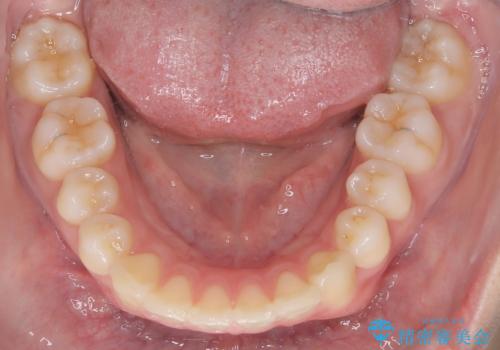

【ワイヤー矯正】前歯の真ん中を合わせたい。

- 前歯が出ている事を主訴に来院されました。

上と下の前歯がずれているため、抜歯を行い前歯の真ん中を合わせる治療計画を立ててワイヤー矯正にて治療を行いました。

途中、矯正用のアンカースクリューを使うことで、最終的にきれいに前歯の真ん中を合わせることができました。

2年という矯正期間でしたが、かみ合わせも良くなりを患者様には満足していただくことができました。